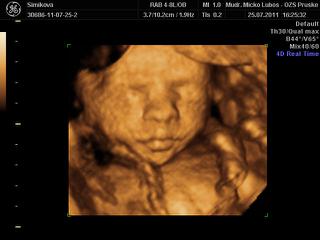

dnes som sa objednala na 3D do hlohovca, som strasne zvedava a nedockava co cakame, hned mi dali termin 9cakala som , ze budem 3tyz cakat), ale ideme uz vo stvrtok. Som zvedava, niako niesom nadcena 3Dckami, sa mi foto deticiek nepaci, take stlacene kadejake.... ani s malym som nebola, ale u neho som vedela, ze chlapec to bude, no tento pocit, ze neviem ma nici, nic si nemozem chystat 😝